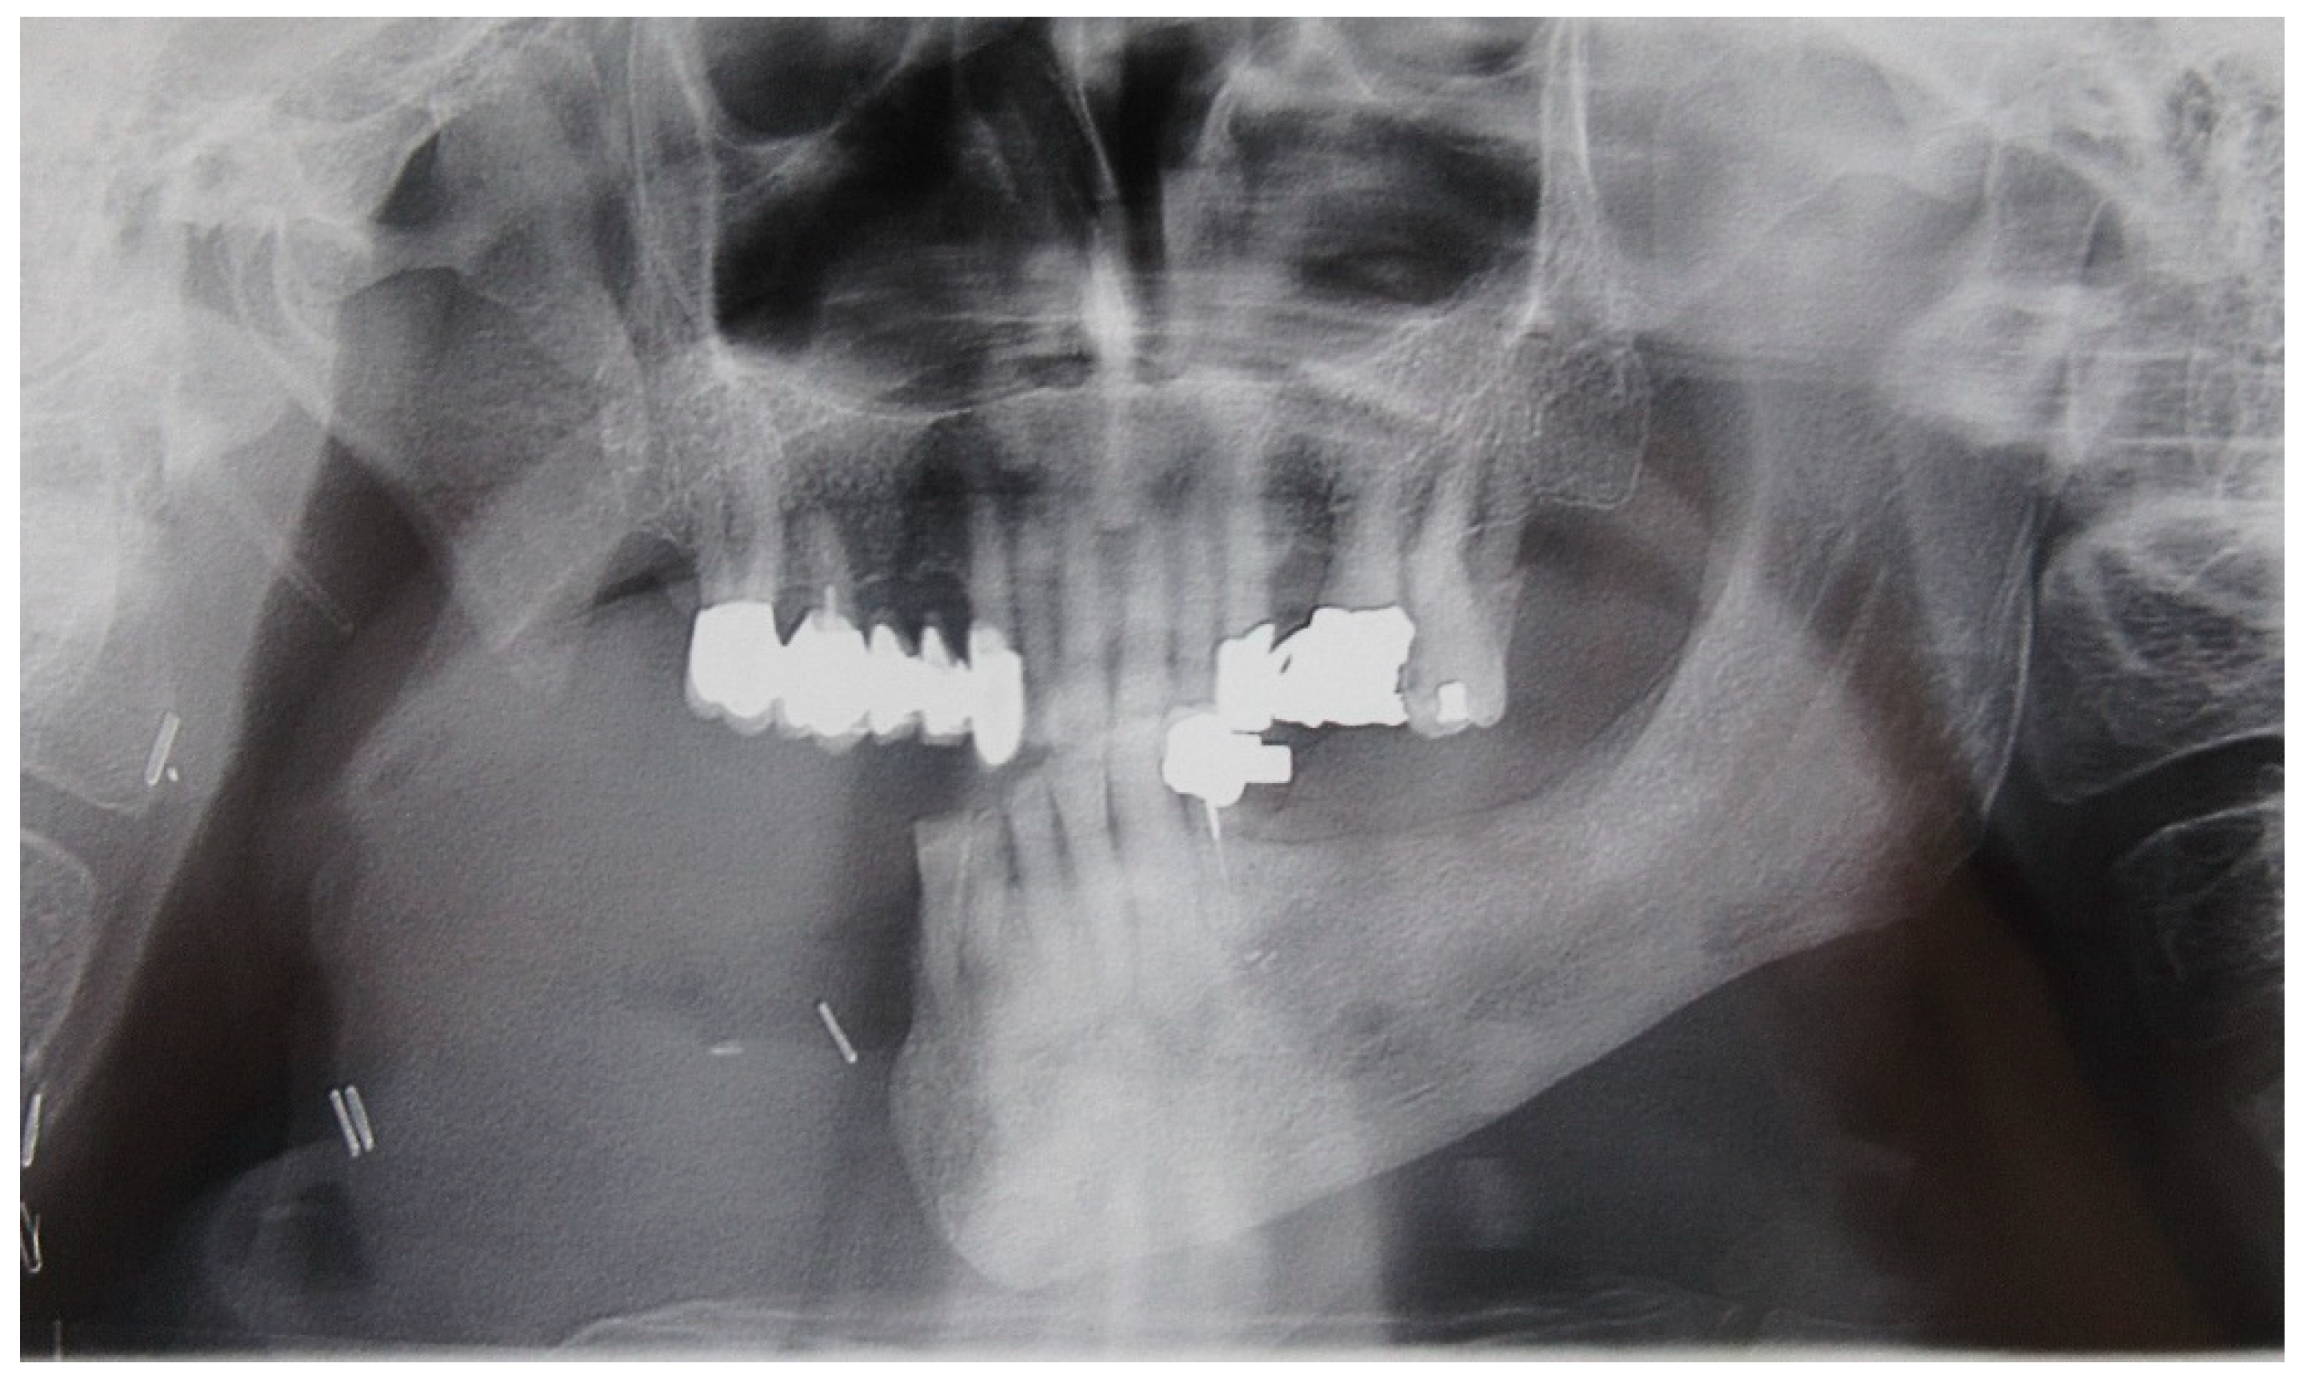

The patient of case 5 displayed a moderate latero-deviation following an L2-3 hemimandibulectomy with partial resection of the coronoid process (Figure 21 and Figure 22). Photos of interocclusal contact between the upper and lower teeth were not feasible due to the patient being unable to successfully close her mouth with the dental gag inserted.

The patient’s surviving teeth (32, 33, 34, 35) are not sufficient to stabilize and counteract the deviation towards the affected side, which not only develops on the transverse plane (left to right) but also on the frontal plane (back to front).

Figure 22. Patient with L2,3 hemimandibulectomy in orthopanoramic X-ray.